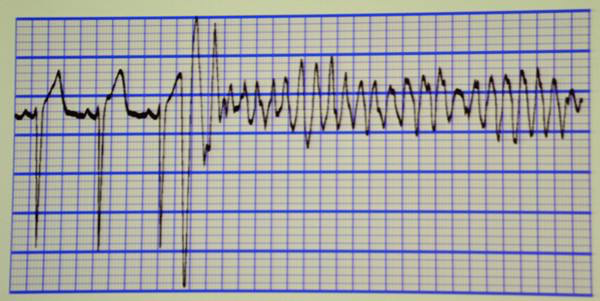

据了解,黄先生在5年前曾因阵发性心悸于深圳其他医院就诊过,诊断为“预激综合征,阵发性室上速”,但未予治疗,在院心电图也的确提示黄先生患有A型预激综合征。预激综合征是什么呢?李海鹰主任指出预激综合征是指心房部分激动由正常房室传导系统以外的先天性附加通道(旁道)下传,使心室某一部分心肌预先激动(预激) ,导致以异常心电生理和(或)伴发多种快速型心律失常为特征的一种综合征。发生预激的解剖学基础是,在正常的房室传导组织以外,存在一些异常的心肌纤维组成的肌束,即旁道 。 简单点说就是,心脏里多了一条捷径,而这条捷径导致患者的心脏某一部分在正常的心脏跳动之前提前跳动了,从而导致心律失常的发生。而预激综合征伴房颤可引起室颤,从而导致心跳呼吸骤停。结合患者相关病史,考虑黄先生存在这种病因的可能,同时,患者心电图提有ST-T改变,心肌标记物明显升高,冠心病不能除外,也不能排除是否有遗传性的致心律失常性心肌病。病因究竟是哪一个,还需进一步冠脉造影及心电生理检查进一步排查。

李海鹰主任是全国电生理专家,在电生理方面有很深的造诣,在心律失常及冠心病的诊治有丰富的经验,电生理及冠脉造影均为微创检查,对正常人来说并不会造成什么影响,但黄先生基本情况差,全身多器官功能不全,他能承受得了这些微创检查吗?另一方面,患者病因未除,病情随时可能进一步恶化,诱发恶性心律失常,患者会有很大的生命危险。情况进击,李海鹰主任决定尽快择期为患者进行相关检查,为了保证患者安全,李主任请了院内多个相关科室的专家会诊,一起商讨治疗方案,提高患者的耐受能力,再三斟酌之后,最后李主任决定先行电生理检查,尽可能帮助患者找到预激的“旁道”并关掉这条“旁道”,再行冠脉造影检查,但在这之前,还需要在密切关注下调整患者的身体状况,尽可能的恢复各脏器的功能。一切准备就绪,李主任带领团队于3月10日为患者行心内电生理检查,成功找到“旁道”,并予射频消融消除旁道,重复刺激,未见预激波,表明患者的预激“旁道”被李主任成功消除了!手术取得成功,黄先生亦无特殊不适,安返病房。